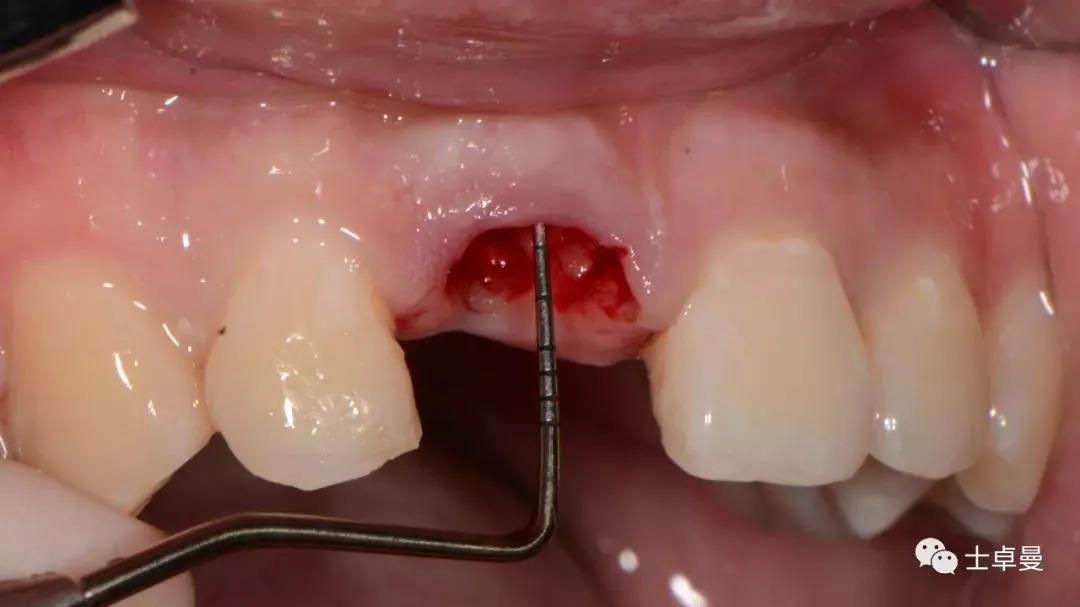

分根

拔出腭侧牙根

保留唇侧牙片

牙周探针探查牙片位置及松动度